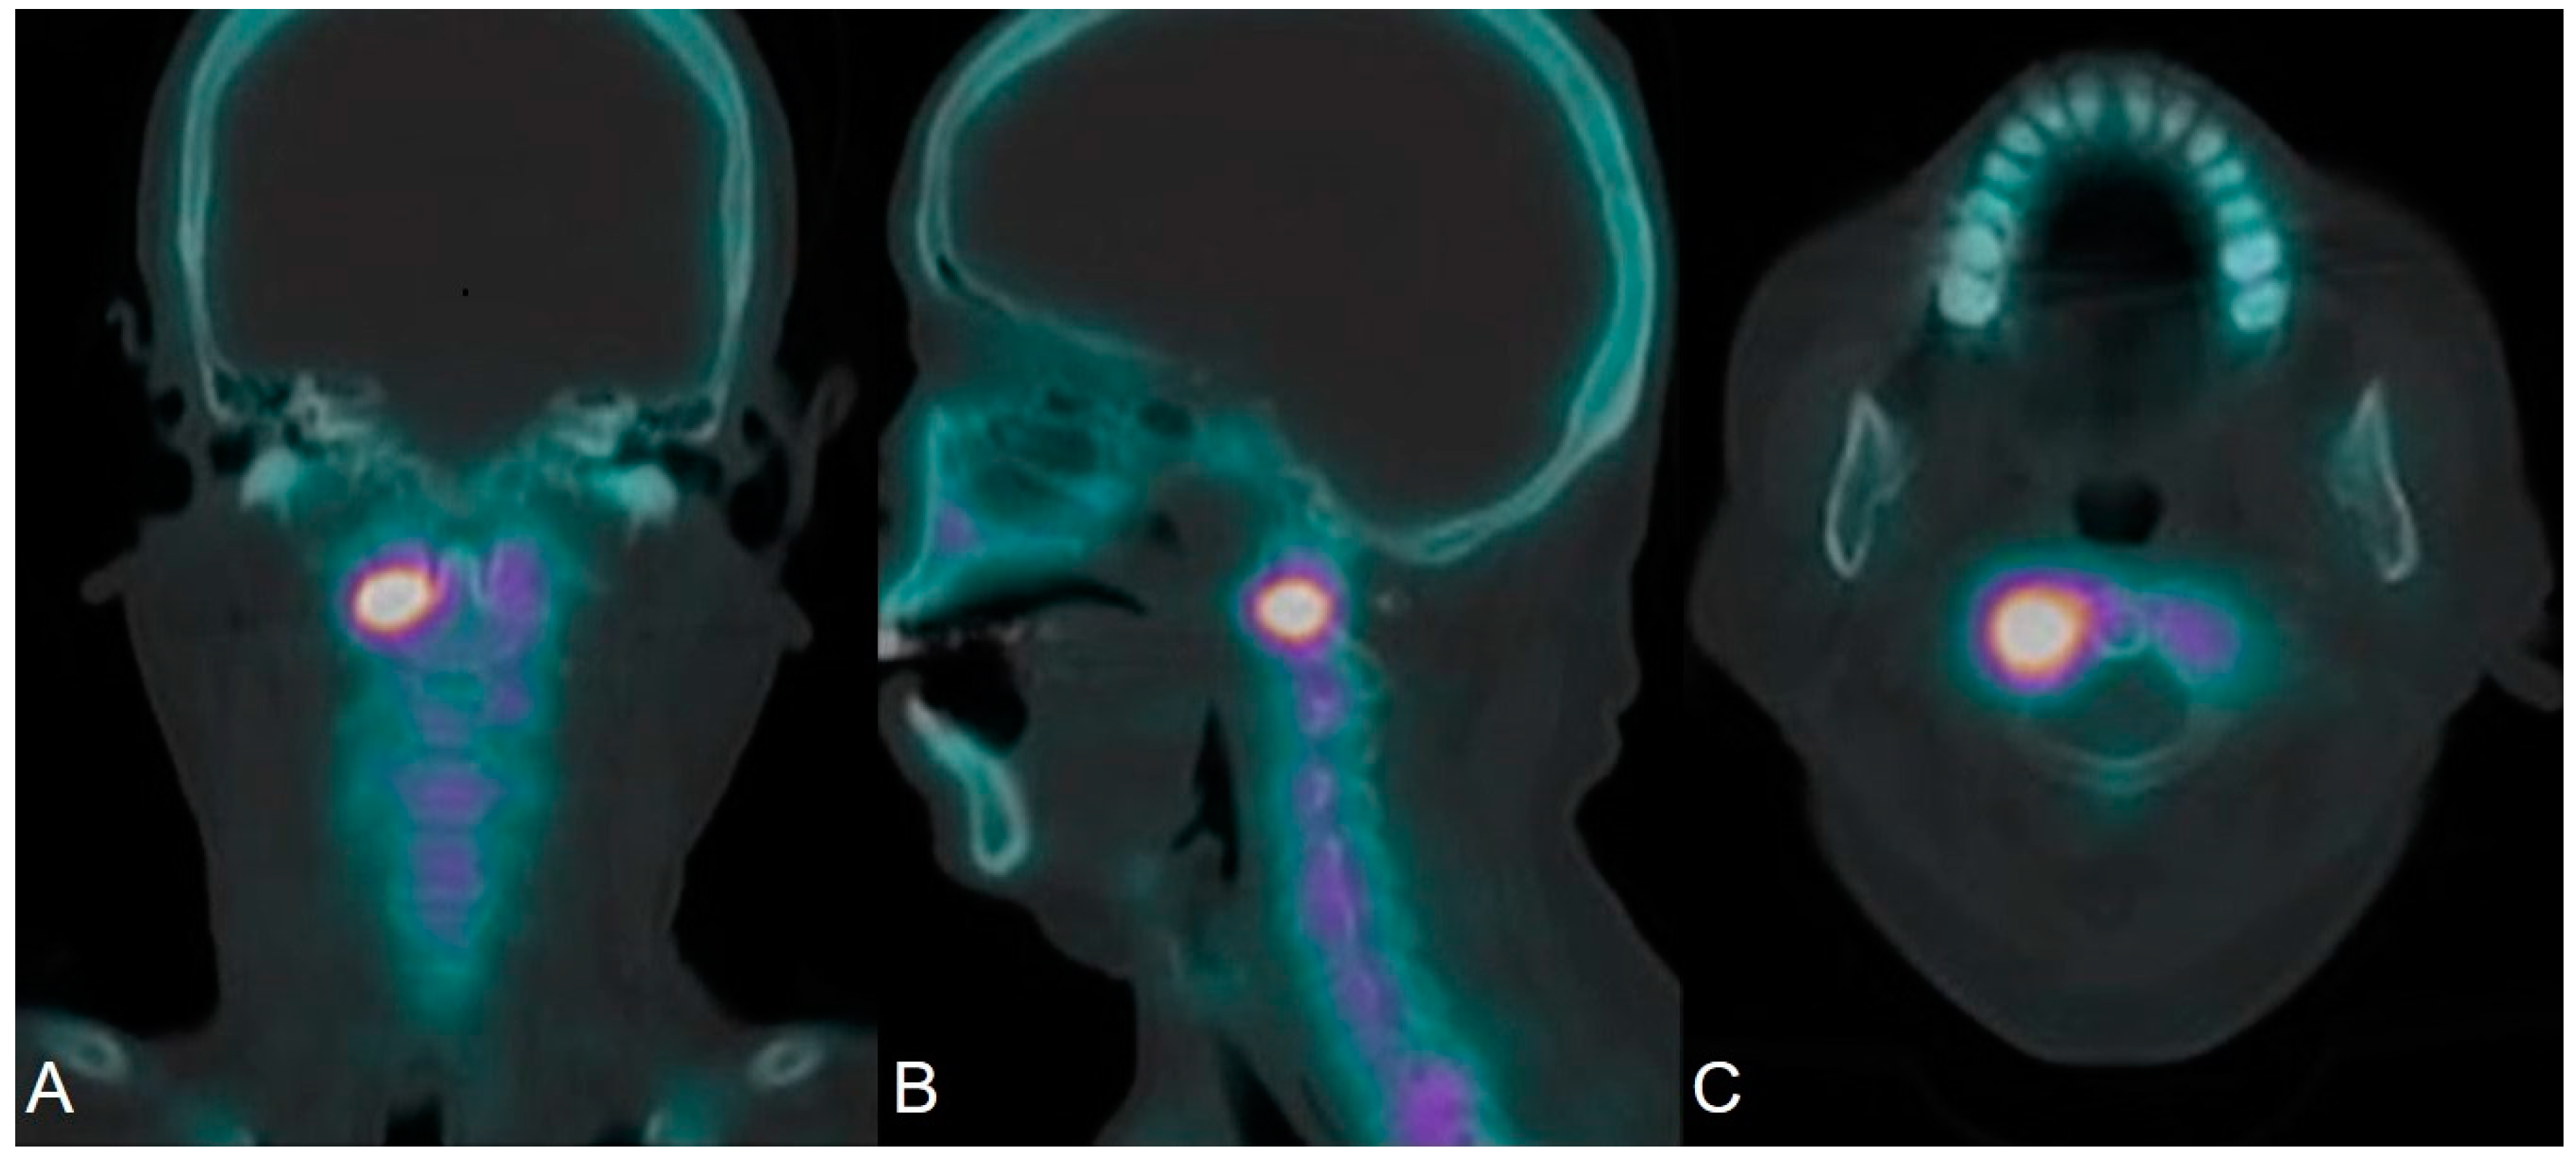

2.4. SPECT/CT